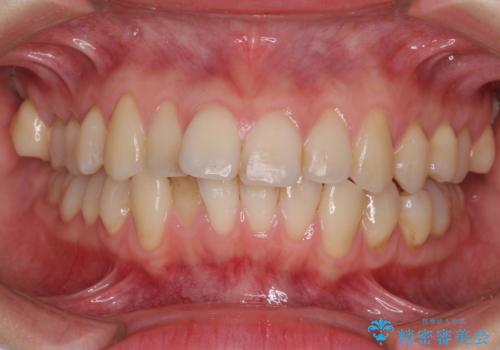

- 上下前歯のデコボコを気にして来院された患者様です。

インビザラインによる上下歯列の側方拡大と後方移動、IPR(歯と歯の間を削る)にるスペースの獲得により歯列を整えることとしました。